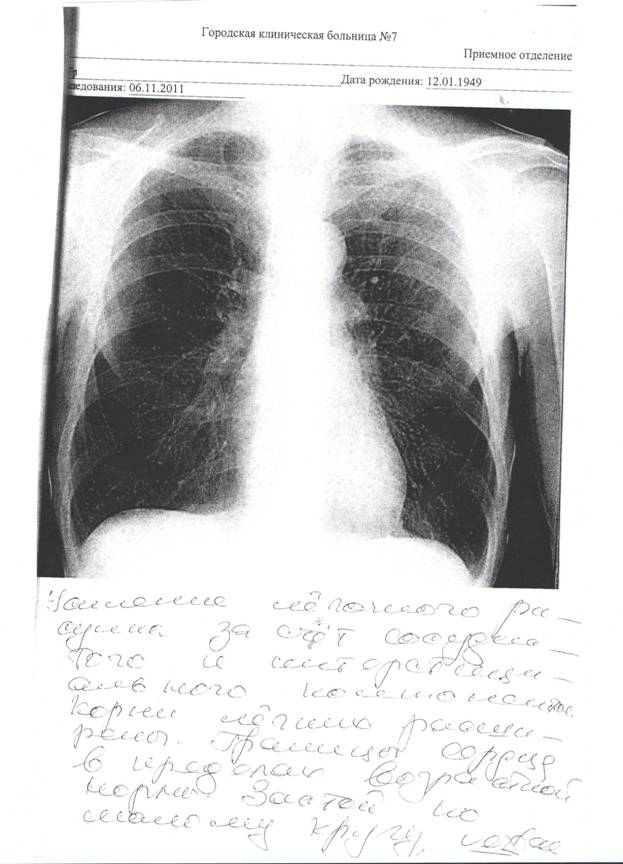

Ультразвуковое исследование сердца и внутренних органов не выявило значительных патологических изменений. При колоноскопии и компьютерной томографии онкологическое заболевание не обнаружено. Данные рентенографии грудной клетки на рис.1.

Рисунок 1 Рентгенограмма больного Г.